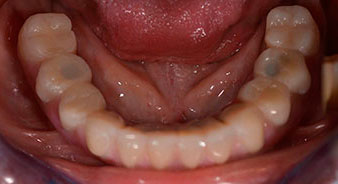

Die 64-jährige Patientin wurde mit einer Unterkiefer-Restbezahnung 38, 33 und 43 und einer klammerbefestigten Interimsprothese im Unterkiefer vorstellig (Abb. 1 und 2).

Nach der Aufklärung über die verschiedenen Möglichkeiten der Versorgung entschied sich die Patientin für eine Extraktion der Restbezahnung im Unterkiefer, eine Sofortimplantation und Versorgung mit der sogenannten Fast & Fixed-Methode (bredent medical). Hierbei wird der provisorische festsitzende Zahnersatz bereits am OP-Tag auf vier Implantaten verschraubt. Das Ziel war, die Patientin am Freitag zu operieren, sodass sie am Montag darauf an den mündlichen Abiturprüfungen teilnehmen konnte.